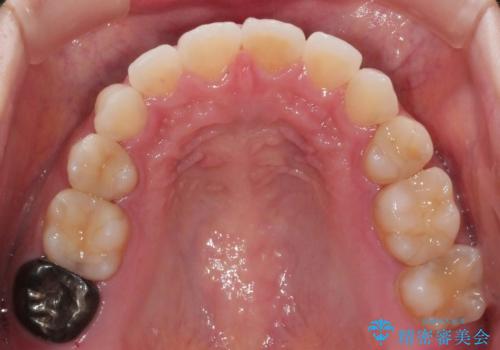

前歯のガタつきを改善 抜歯矯正後の後戻り

- 抜歯矯正後の後戻りで前歯ガタつきが主訴で来院された患者様です。

後戻りの程度としては軽度なので、治療期間としては短く終えることが出来ました。

前歯の正中線も改善され大変満足して頂きました。